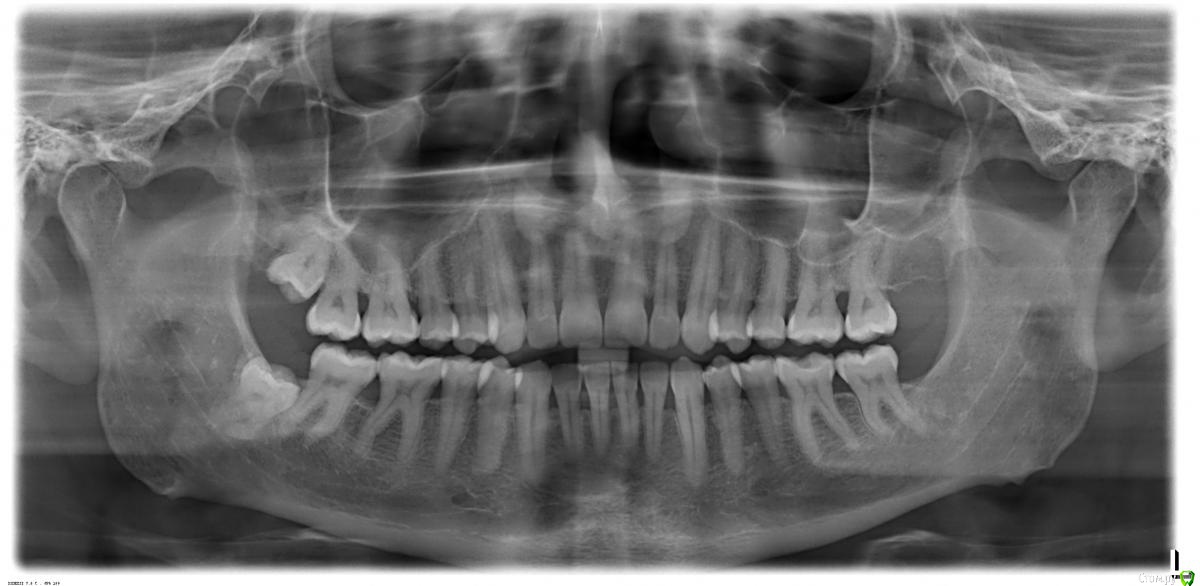

red_butler Опубликовано 24 сентября, 2019 Поделиться Опубликовано 24 сентября, 2019 Это про пародонтальные карманы Ссылка на комментарий

Jurai Опубликовано 26 сентября, 2019 Поделиться Опубликовано 26 сентября, 2019 Вам требуется тщательная диагностика у пародонтолога, оценка статуса и причин пародонтита и, исходя из полученных данных, комплексное лечение. Ссылка на комментарий